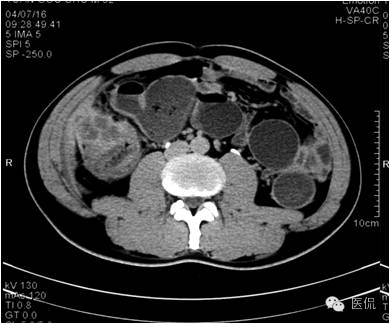

门脉期上述部位持续强化,程度加重,且环壁影增厚,核心样结节、分隔明显。

延迟期密度略有下降,但仍有强化,形态不规则。